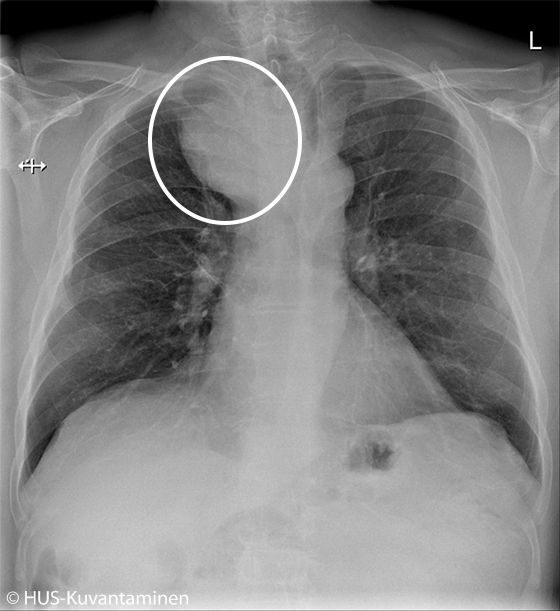

Kookas struumakyhmy keuhkokuvassa.

Potilaan keuhkokuva tarkistettiin pitkittyneen flunssan vuoksi. Oireita selittävää syytä ei löytynyt, mutta kuvassa näkyy ylämediastinumin massa, jonka vuoksi trakea devioi vasemmalle. Keuhkokudoksessa ei ole aktuellia ja hilusalueet sekä keuhkosopet ovat siistit. Kuvan löydös oli aihe jatkotutkimuksille. Ultraäänitutkimuksessa todettiin retrosternaalisesti ulottuva kookas oikea kilpirauhaslohko, joksi thoraxkuvan muutoskin sopii.